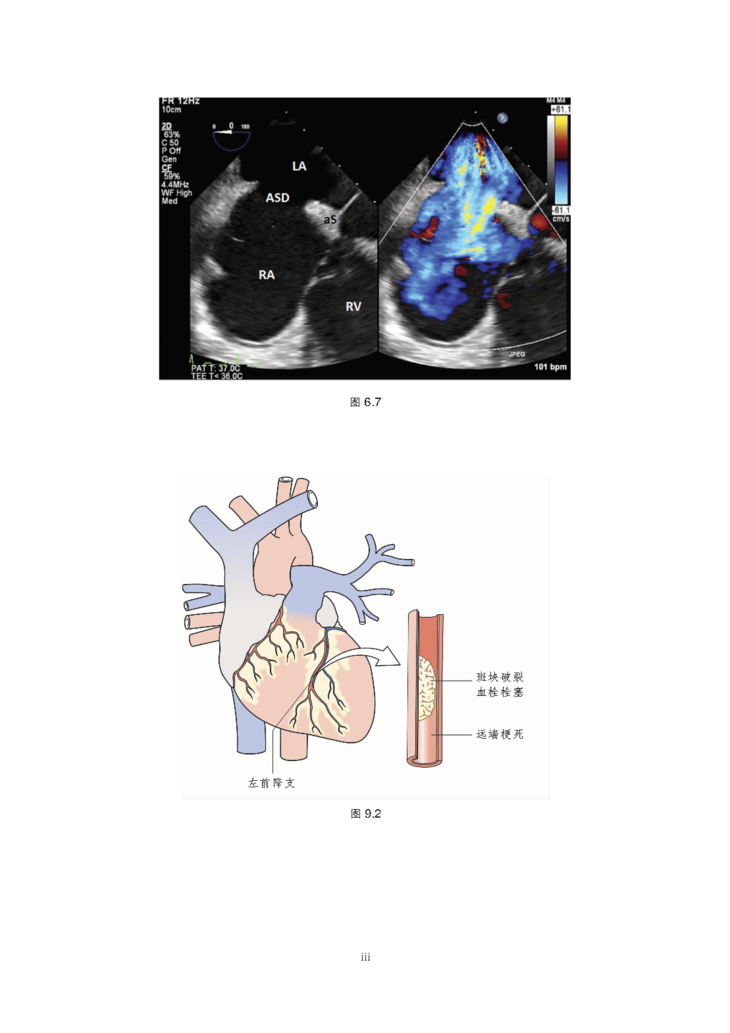

本书为心脏病学临床指导性用书,主要从体格检查、患者主诉分析、常见心血管疾病分类、辅助检查、介入治疗及药物治疗6部分对临床心血管疾病诊疗进行了系统介绍,各章辅以要点、图表和流程图等形式阐释了心脏病学的基本概念和重要临床表现,是一本适用于广大心血管内科医生和医学生的案头必备书。

2.涵盖常用检查技术、常见疾病、影像学方法(包括胸片、MRI和CT)、介入治疗和药物。